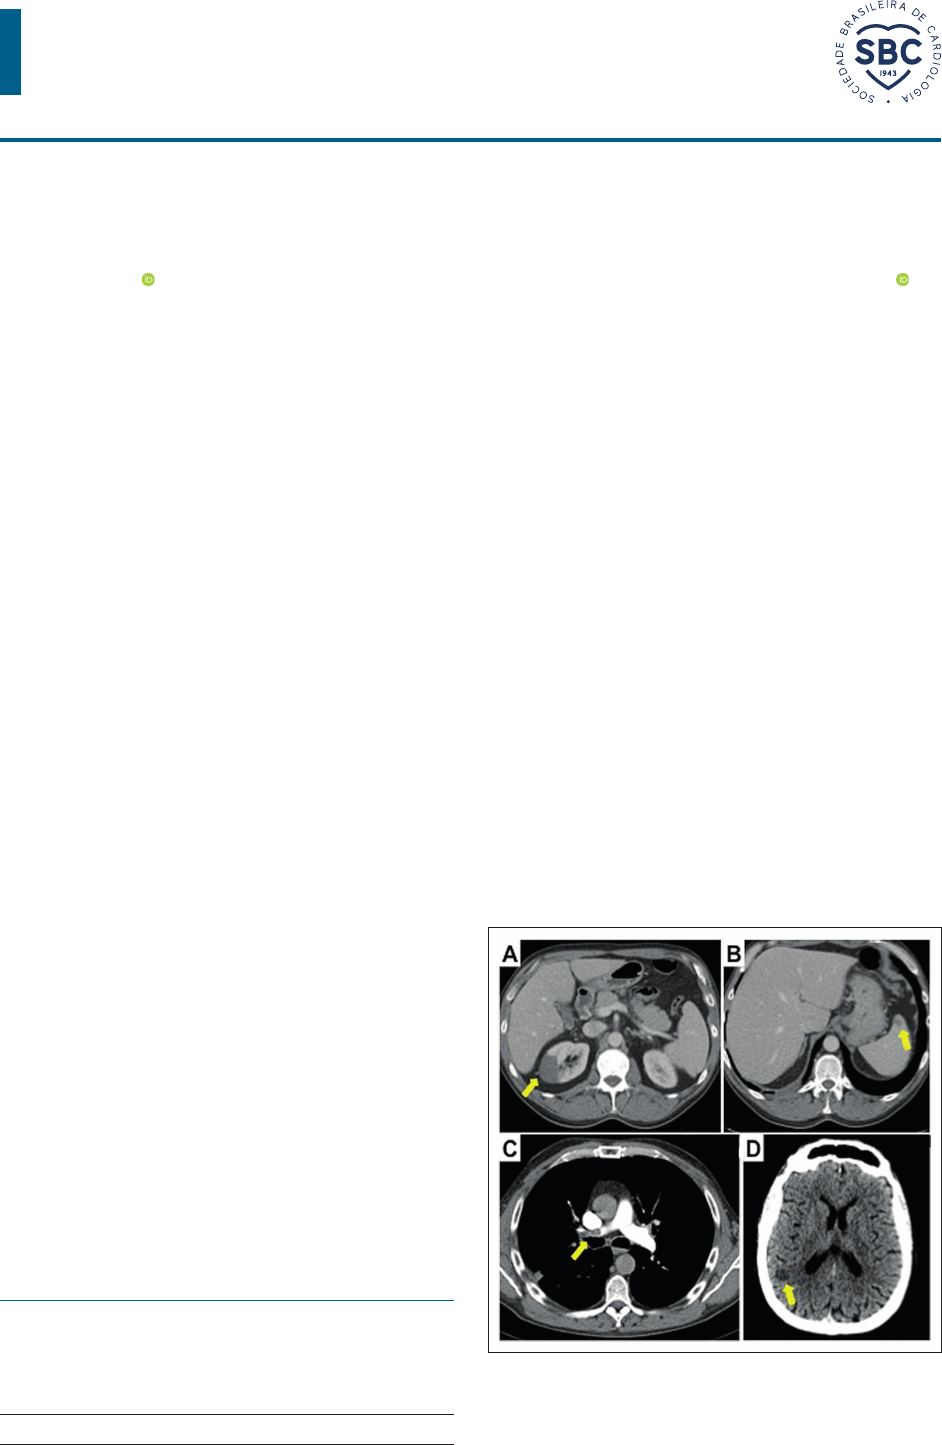

<p>Arq Bras Cardiol. 2022; 119(6):996-998</p><p>Carta Científica</p><p>Trombose Ventricular Esquerda e Tromboembolismo Pulmonar em</p><p>um Paciente de Covid-19 Assintomático</p><p>Left Ventricular Thrombosis and Pulmonary Thromboembolism in an Asymptomatic Covid-19 Patient</p><p>Natalia Lorenzo,1 Veronica Hernandez,1 Alvaro Montes,2 Fernando Rivero,2 Guillermo Reyes,2 * Rio Aguilar2</p><p>Hospital Universitario Infanta Cristina - Cardiologia,1 Parla – Espanha</p><p>Hospital Universitario de la Princesa - Cardiologia e Cirurgia Cardíaca,2 Madrid – Espanha</p><p>A COVID-19 (doença do coronavírus) é a síndrome</p><p>associada à infecção síndrome respiratória aguda grave</p><p>coronavírus 2 (SARS-CoV-2). Embora a insuficiência</p><p>respiratória seja a característica mais aparente da doença,</p><p>a trombose venosa e arterial são complicações bem</p><p>reconhecidas. Sabe-se que pacientes de COVID-19 ativam</p><p>várias respostas inflamatórias e coagulatórias sistêmicas que</p><p>são vitais para a defesa do hospedeiro, mas podem levar</p><p>a situações deletérias, principalmente para os pacientes</p><p>internados em unidades de terapia intensiva. Este relato de</p><p>caso apresenta múltiplos eventos embólicos com trombose</p><p>do ventrículo esquerdo e coincidência de tromboembolismo</p><p>pulmonar em um paciente com infecção por COVID-19</p><p>assintomática e sem doença cardiovascular preexistente.</p><p>Carta Científica</p><p>Um homem de 48 anos chegou ao atendimento de</p><p>emergência com dor abdominal e vômito com duração de</p><p>12 horas. O paciente teve um histórico de trombose venosa</p><p>porto-esplênica dez anos antes da admissão, foi tratado por</p><p>6 meses com anticoagulação oral e considera-se que isso</p><p>se devia a uma deficiência moderada de proteína C, que</p><p>não foi confirmada em exames laboratoriais subsequentes.</p><p>Os sinais vitais estavam normais; ele estava afebril e não</p><p>houve achados significativos no exame físico, exceto por</p><p>dor no lado esquerdo à apalpação. O teste de reação em</p><p>cadeia da polimerase via transcriptase reversa (RT-PCR) para</p><p>COVID-19 foi negativo. Os exames de sangue mostraram</p><p>elevação significativa dos reagentes de fase aguda (proteína</p><p>C reativa: 138,3 mg/L, fibrinogênio > 500 mg/dL e leucócitos</p><p>12,99 10^3/μL). Os parâmetros de coagulação estavam</p><p>dentro da faixa normal: o tempo de protrombina (TP) foi</p><p>de 12,1 segundos, o tempo de tromboplastina parcial (PTT)</p><p>foi de 36,3 segundos, a atividade de protrombina (AP) foi</p><p>de 86%, a razão normalizada internacional (RNI) 1,08 e</p><p>plaquetas 326.000/μL.</p><p>O ultrassom abdominal não revelou achados relevantes,</p><p>e, portanto, foi realizada uma tomografia computadorizada</p><p>(TC). A TC abdominal encontrou múltiplos infartos no rim</p><p>direito (Figura 1A) e isolados no baço (Figura 1B). Além</p><p>disso, observou-se um defeito de enchimento no ventrículo</p><p>esquerdo (Figura 2A). O ecocardiograma transtorácico</p><p>confirmou a presença de uma massa móvel hiperecogênica</p><p>e homogênea (3,1 x 2 cm) com bordas regulares (Figuras</p><p>2A, 2B, 2C), ancorado ao terço intermediário do septo do</p><p>ventrículo esquerdo (VE). A anatomia do VE estava normal,</p><p>com dimensões normais e fração de ejeção normal sem</p><p>anormalidades na movimentação da parede.</p><p>A TC do tórax também revelou tromboembolismo</p><p>pulmonar, sem um efeito de enchimento originado na</p><p>artéria pulmonar principal direito (Figura 1C), associado</p><p>a infarto pulmonar no lóbulo superior direito; e a TC</p><p>cerebral detectou uma lesão isquêmica subaguda na</p><p>junção parieto-occipital (Figura 1D). Com o diagnóstico do</p><p>tromboembolismo pulmonar e provavelmente de trombo</p><p>Palavras-chave</p><p>COVID-19/complicações; SARS-COV-2; Embolia</p><p>Pulmonar; Disfunção do Ventrículo Esquerdo; Infarto do</p><p>Miocárdio; Síndrome Respiratória Aguda Grave/complicações;</p><p>Diagnóstico por Imagem/métodos</p><p>Correspondência: Rio Aguilar •</p><p>Hospital Universitario de la Princesa. C/ Diego de León, 62. Madrid 28006.</p><p>Espanha</p><p>E-mail: rioaguilartorres@gmail.com</p><p>Artigo recebido em 15/08/2021, revisado em 19/03/2022,</p><p>aceito em 01/06/2022</p><p>DOI: https://doi.org/10.36660/abc.20210590</p><p>Figura 1 – A) Tomografia computadorizada (TC) abdominal. Infarto do</p><p>rim direito (seta). B) TC abdominal. Infarto no baço). C) TC cerebral.</p><p>Lesão isquêmica na junção parieto-occipital direita (seta). D) TC do</p><p>tórax. Defeito de enchimento originado na artéria pulmonar principal</p><p>direita (seta).</p><p>996</p><p>https://orcid.org/0000-0002-3477-9433</p><p>https://orcid.org/0000-0002-6731-0156</p><p>mailto:rioaguilartorres@gmail.com</p><p>Arq Bras Cardiol. 2022; 119(6):996-998</p><p>Carta Científica</p><p>Lorenzo et al.</p><p>Trombose Múltipla em Paciente de Covid-19 Assintomático</p><p>no ventrículo esquerdo com múltiplas lesões embólicas,</p><p>o paciente foi submetido a cirurgia cardíaca para retirar a</p><p>massa. Embora o eletrocardiograma estivesse normal e as</p><p>troponinas cardíacas estivessem dentro da faixa normal,</p><p>foi realizada uma angiografia coronária invasiva no pré-</p><p>operatório, que não revelou doença arterial coronariana</p><p>aterosclerótico ou embolia coronária. O ecocardiograma</p><p>transesofágico intraoperatório mostrou dilatação do tronco</p><p>pulmonar, com a presença de uma imagem compatível</p><p>com trombo no ramo pulmonar direito (Figura 2F). Além</p><p>disso, a comunicação interatrial e o forame oval patente</p><p>foram excluídos após uma ecografia com contraste</p><p>com microbolhas. Foi realizado um novo teste RT-PCR</p><p>para COVID-19 2 dias após a admissão hospitalar, com</p><p>resultado positivo (variante Alfa [B.1.1.7], comumente</p><p>chamada de variante britânica). Após alguns dias a</p><p>presença da COVID-19 foi confirmada no IgG. O paciente</p><p>não teve sintomas de infecção e nenhum momento.</p><p>A maioria da massa pode ser retirada com cirurgia</p><p>(Figura 2G), e a anatomia patológica confirmou que era um</p><p>trombo (Figura 2H). A evolução subsequente foi favorável</p><p>na anticoagulação com enoxaparina. Novos exames</p><p>laboratoriais para avaliar a presença de uma coagulopatia</p><p>mostraram deficiência leve de proteína C.</p><p>A presença de trombos cardíacos no ventrículo</p><p>esquerdo é uma condição comum em pacientes com</p><p>infarto do miocárdio (IM) (15-25%) e no surgimento de</p><p>Figura 2 – A) TC do tórax. Defeito de enchimento no ventrículo esquerdo (seta). B) Ecocardiograma transtorácico 2D. Vista de 4 eixos Massa hiperecogênica</p><p>pedunculada (seta). C) Ecocardiograma transtorácico 2D. A massa (seta) em vista de eixo curto. D) Ecocardiograma transtorácico 3D. Massa ancorada</p><p>no septo do ventrículo esquerdo (seta). E) Ecocardiograma transesofágico 2D. Vista de 4 câmaras. Massa ancorada no septo do ventrículo esquerdo</p><p>(seta). F) Trombo no ramo pulmonar direito (seta). G) Peça cirúrgica retirada do ventrículo esquerdo. H) Anatomia patológica do trombo.</p><p>cardiomiopatia dilatada (até 36%) quando detectada com</p><p>as modalidades de imagens ideais.1,2 Entretanto, há apenas</p><p>relatos episódicos em VE com estrutura normal, mesmo na</p><p>presença de uma trombofilia.3-5</p><p>A coagulopatia, na forma de trombose venosa e arterial,</p><p>é uma das sequelas mais graves da infecção por SARS-</p><p>CoV-2, e foi associada a resultados ruins. Relatórios de alta</p><p>incidência de trombose, apesar do uso de anticoagulante</p><p>em doses profiláticas e terapêuticas levantam perguntas</p><p>sobre uma fisiopatologia exclusiva da COVID-19.</p><p>As hipóteses propostas incluem uma resposta inflamatória</p><p>gravemente aumentada que leva à trombo-inflamação,</p><p>por mecanismos tais como as tempestades de citocina,</p><p>ativação do complemento e endotelite.6-9 Também já se</p><p>sugeriu que o próprio vírus tem a possibilidade de ativar</p><p>a cascata de coagulação.10</p><p>Embora a trombose seja frequentemente vista no cenário</p><p>de pacientes com COVID-19 que estão em um estágio crítico</p><p>da doença, eventos tromboembólicos importantes são raros</p><p>em pacientes assintomáticos e infecções leves.11 Entretanto,</p><p>até onde sabemos, não há relatos anteriores de trombose</p><p>em vários locais, incluindo trombos no VE, em pacientes</p><p>completamente assintomáticos do ponto de vista da infecção</p><p>sem doença cardiovascular preexistente. Acreditamos que,</p><p>em nosso paciente, a presença de uma coagulopatia prévia</p><p>teve um papel relevante nessa forma rara de apresentação</p><p>em um paciente com COVID-19.</p><p>997</p><p>Arq Bras Cardiol.</p><p>2022; 119(6):996-998</p><p>Carta Científica</p><p>Lorenzo et al.</p><p>Trombose Múltipla em Paciente de Covid-19 Assintomático</p><p>1. Lattuca B, Bouziri N, Kerneis M, Portal JJ, Zhou J, Hauguel-Moreau M, et al.</p><p>Antithrombotic Therapy for Patients With Left Ventricular Mural Thrombus. J</p><p>Am Coll Cardiol. 2020; 75(14):1676-85. doi: 10.1016/j.jacc.2020.01.057.</p><p>2. Lorenzo N, Restrepo JA, Aguilera MC, Rodriguez D, Aguilar R. Massive</p><p>intraventricular thrombosis in a young woman with idiopathic dilated</p><p>cardiomyopathy. Arq Bras Cardiol. 2015;105(6):647-8. doi: 10.5935/</p><p>abc.20150131.</p><p>3. Maki H, Nishiyama M, Shirakawa M. simultaneous left ventricular and</p><p>deep vein thrombi caused by protein C deficiency. Case Rep Med.</p><p>2017;2017:4242959. doi.org/10.1155/2017/4240959</p><p>4. Pahuja M, Ainapurapu B, Abidov A. Large left ventricular thrombus in</p><p>a patient with systemic and venous thromboembolism secondary to</p><p>protein C and S deficiency. Case Rep Cardiol 2017;2017:7576801. doi:</p><p>10.1155/2017/7576801.</p><p>5. Reddy S Ziady GM, Zerbe T, Matesic C, Griffith B. Recurrence of a left</p><p>ventricular thrombus after surgical excision in a young patient with normal</p><p>left ventricular systolic function. A case report. Angiology. 1993;44(11):923-</p><p>8. DOI: 10.1177/000331979304401113</p><p>6. Klok FA, Kruip MJHA, van der Meer NJM, Arbous MS, Gommers DAMPJ,</p><p>Kant KM et al. Incidence of thrombotic complications in critically ill ICU</p><p>patients with COVID-19. Thromb Res. 2020;191:145-7. doi: 10.1016/j.</p><p>thromres.2020.04.013</p><p>7. Lodigiani C, Iapichino G, Carenzo L, Cecconi M, Ferrazzi P, Sebastian T, et al.</p><p>Venous and arterial thromboembolic complications in COVID-19 patients</p><p>admitted to an academic hospital in Milan, Italy. Thromb Res. 2020;191:9-</p><p>14. DOI: 10.1016/j.thromres.2020.04.024</p><p>8. Abou-Ismail MY, Diamond A, Kapoor S, Arafah Y, Nayak L. The hypercoagulable</p><p>state in COVID-19: Incidence, pathophysiology, and management. Thromb</p><p>Res. 2020;194:101-15.doi: 10.1016/j.thromres.2020.06.029.</p><p>9. Guan WJ, Ni ZY, Hu Y, Liang WH, Ou CQ, He JX, et al. Clinical characteristics</p><p>of coronavirus disease 2019 in China. N Engl J Med. 2020;382(18):1708-20.</p><p>DOI: 10.1056/NEJMoa2002032</p><p>10. Oudkerk M, Büller HR, Kuijpers D, van Es N, Oudkerk SF, McLoud T, et al.</p><p>Diagnosis, prevention, and treatment of thromboembolic complications in</p><p>covid-19: report of the National Institute for Public Health of the Netherlands.</p><p>Radiology. 2020;297(1):E216-E222. DOI: 10.1148/radiol.2020201629</p><p>11. Zheng H, Stergiopoulos K, Wang L. Chen L. Cao J. COVID-19 presenting</p><p>as major thromboembolic events: Virchow’s Triad revisited and clinical</p><p>considerations of therapeutic anticoagulation. Cureus. 2020;12(8):e10137.</p><p>DOI: 10.7759/cureus.10137</p><p>Referências</p><p>Este é um artigo de acesso aberto distribuído sob os termos da licença de atribuição pelo Creative Commons</p><p>Contribuição dos autores</p><p>Concepção e desenho da pesquisa: Lorenzo N;</p><p>Obtenção de dados: Lorenzo N, Hernandez V, Montes</p><p>A, Rivero F, Reyes G, Aguilar R; Análise e interpretação</p><p>dos dados: Lorenzo N, Hernandez V, Aguilar R; Redação</p><p>do manuscrito: Lorenzo N, Aguilar R; Revisão crítica do</p><p>manuscrito quanto ao conteúdo intelectual importante:</p><p>Lorenzo N, Hernandez V, Aguilar R.</p><p>Potencial conflito de interesse</p><p>Não há conflito com o presente artigo.</p><p>Fontes de financiamento</p><p>O presente estudo não teve fontes de financiamento</p><p>externas.</p><p>Vinculação acadêmica</p><p>Não há vinculação deste estudo a programas de pós-</p><p>graduação.</p><p>Aprovação ética e consentimento informado</p><p>Este artigo não contém estudos com humanos ou animais</p><p>realizados por nenhum dos autores.</p><p>998</p>